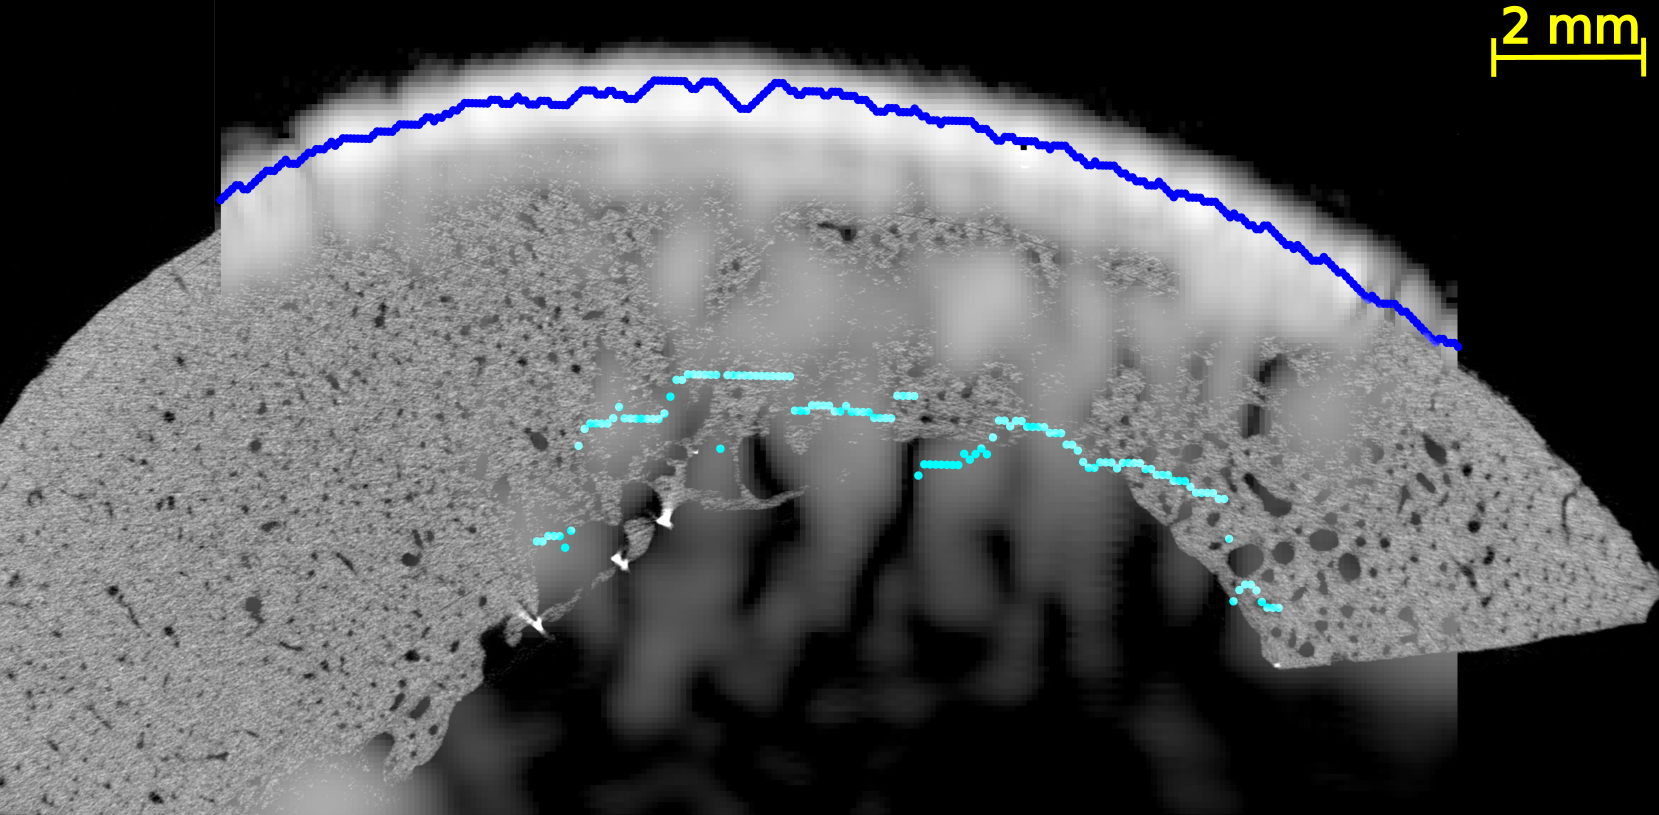

In all US images (Figure 4 and Figures S2-5 of supplementary materials), the periosteal surface appeared as a very bright line. The brightness of the endosteal surface was found to decrease with increasing porosity and with the presence of large pores. The endosteal surface was relatively bright in Samples 1 and 2 which had a small number of large pores and a small porosity; while the contrast of the endosteal surface was relatively weak in Samples 3 and 5 which had a higher porosity and some large pores near the endosteal surface (see the HR-µCT images (panels (a), (d), (g) and (j) of Figure 4). Segmentation with Dijkstra’s algorithm successfully delineated periosteal and endosteal surfaces for all measurement zones in all samples (see Figure 4). US images were aligned on HR-µCT images based on the periosteal surface segmentation. Periosteal surfaces from the US images accurately matched the periosteal surfaces segmented from the HR-µCT images: for all VOIs and all measurement repetitions, the root mean square error (RMSE) between the two segmentations was smaller than 0.3 mm, which value corresponds to half a US wavelength in water at 2.5 MHz (i.e., approximately the resolution limit).

We observed a good match between the segmented endosteal surface in the US image and the boundary of the cortex as seen in the HR-µCT image. The segmented endosteal surface closely followed the shape of the bone in the samples 1 and 2 which were the less porous and less heterogeneous. It is noteworthy that, despite the large thickness and complex geometry of sample 2, the endosteal surface was very bright in the US image. In the more porous and heterogeneous samples 3 and 5, the segmented endosteal surface followed the gross shape of the bone but was inside the cortex as seen in the HR-µCT image, above some large pores found close to the endosteal cortex boundary.

We evaluated the quality of US anatomical reconstructions and wave speed measurements across sixteen VOIs from bones of four individuals. Indeed, the bone of a fifth individual (sample 4) was too porous and heterogeneous to be effectively imaged through US. Our results indicate that the cortex boundaries and cortical thickness can be accurately determined for homogeneous and moderately porous VOIs, even for a thick cortex, as observed in samples 1 and 2 (mean thickness 2.9 and 5.9 mm and porosity between 5.0 and 12.3%, respectively). In these cases, the overlaying of US and HR-CT images showed that the segmentation of the surfaces in US images with the Dijkstra’s method closely aligns with the actual boundary, achieving thickness measurements with mean relative errors of 9 % and 4 %, respectively. In regions with higher porosity and larger pore diameters (samples 3 and 5 with porosity between 10.9 and 16.6% and Lg.Po.Dm between 224 and 307 m, respectively), the brightness of the endosteal surface is significantly reduced (from 7 dB to -5 dB). Nevertheless, Dijkstra’s algorithm was able to delineate endosteal boundaries that generally lied within the cortex, above the region with very large pores nearest to the endosteal surface. Consequently, in these cases, US-based cortical thickness measurements underestimated the reference (mean relative errors of 32 % and 47 %). However, for these highly remodeled bones with large resorption cavities leading to a trabecularization of the endosteal region, the delineation of the endosteal boundary as the end of the cortex and the beginning of the medullary canal is ambiguous, making it challenging to obtain a meaningful estimate of cortical thickness in the HR-CT images [5]. Another limiting factor in comparing cortical thicknesses determined from HR-CT and from US images lies in the slight differences in the regions of interest used for each VOI. The region of interest used for HR-CT images (Figure 2) were slightly larger than that used for US images. In the latter, as shown in Figure 4, the surfaces could only be reconstructed for a limited portion of the cortex due to the finite US probe aperture.

It is noteworthy that the inner cortex surface reconstructed with US was consistently within the bone, indicating that it effectively detects the most compact region corresponding to the tissue above the large pores in the endosteal region.

In highly porous samples exhibiting large pores, the reconstructed endosteal surface may show a reduced brightness and a lack of continuity. Indeed, previous simulations demonstrated that increased pore size has a strong detrimental effect on endosteal interface brightness [29], primarily due to the enhanced scattering by large pores. This ex vivo study corroborates these simulations results by providing an experimental proof that pore size is a major factor influencing intracortical US image quality.